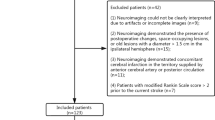

The current diagnostic study had approval from the Institutional Ethics Committee of our hospital (approval number: 2021-008-01 K). Each patient provided written informed consent before MRI examinations. The study was performed in accordance with the 1964 Declaration of Helsinki and its later amendments. From January 2018 to December 2019, a cohort of 598 patients diagnosed with ischemic stroke in our institution were included in this study. The participants had no previous infarction, and could live independently before the infarction. DWI scans were acquired within 24 h following stroke onset. Cases with previous cerebral hemorrhage, brain trauma, previous neurological disorder, and severe MRI artifacts were excluded.

We recorded the demographic and clinical data of all participants, i.e., age, sex, blood pressure, blood sugar, hemorrhage, baseline National Institutes of Health Stroke Scale (NIHSS) score (NIHSSbaseline), NIHSS score at 24 h post-admission (NIHSS24h), and the modified Rankin scale (mRS) score at 90 days. Regarding functional outcomes, the individuals were assigned to the good (mRS score ≤ 2) and poor (mRS score > 2) outcome groups [17, 18].